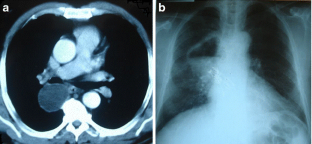

Fig. 1